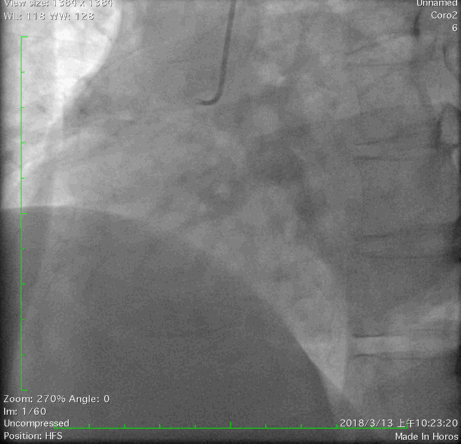

2018年3月13日外院行造影检查示左优势,LAD发出后闭塞,LCX优势型,远端可见与LAD远端形成心外膜侧支,OM1闭塞,RCA闭塞。当地尝试开通RCA和LAD失败,经我院心内、外科联合讨论后,拟心内科介入开通LAD闭塞。

冠脉造影:

右足

右头

蜘蛛位

左头